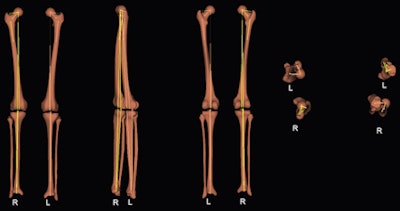

The group took 3D measurements of eight dried bones, analyzing them with the EOS system using stereoscopic software and comparing the measurements with 3D CT. Also, 47 lower limbs of children and adolescents were studied using biplanar low-dose x-ray 2D and 3D measurements. Both parts of the study were evaluated for femoral length, tibial length, femoral mechanical angle, tibial mechanical angle, frontal and lateral knee angulations, and the femoral neck-shaft angle.

The researchers found the 3D comparison between the EOS system and CT showed no significant differences in femoral length, tibial length, femoral mechanical angle, tibial mechanical angle, frontal knee angulation, lateral knee angulation, and femoral neck-shaft angle.

However, 2D and 3D measurements from the EOS system demonstrated significant differences in tibial length, femoral mechanical angle, and femoral neck-shaft angle.

"As 3D measurements provide us with more precise information than 2D measurements, we believe that this technique may be a useful and reliable tool in the assessment of lower extremity alignment in children and adolescents, especially when patients present with significant knee flexion/extension or with rotational deformities," the researchers wrote.